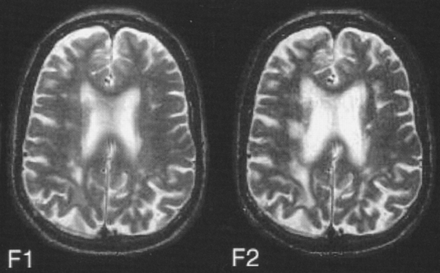

白质hyperintensities和平衡失调

惠特曼et al。跟踪调查了70名健康的老年人,发现一个重要的体积关系恶化的平衡和增加白质高密度核磁共振。这是第一个纵向研究表明hyperintensity体积变化与老年人步态和平衡的变化。

看到页面990年